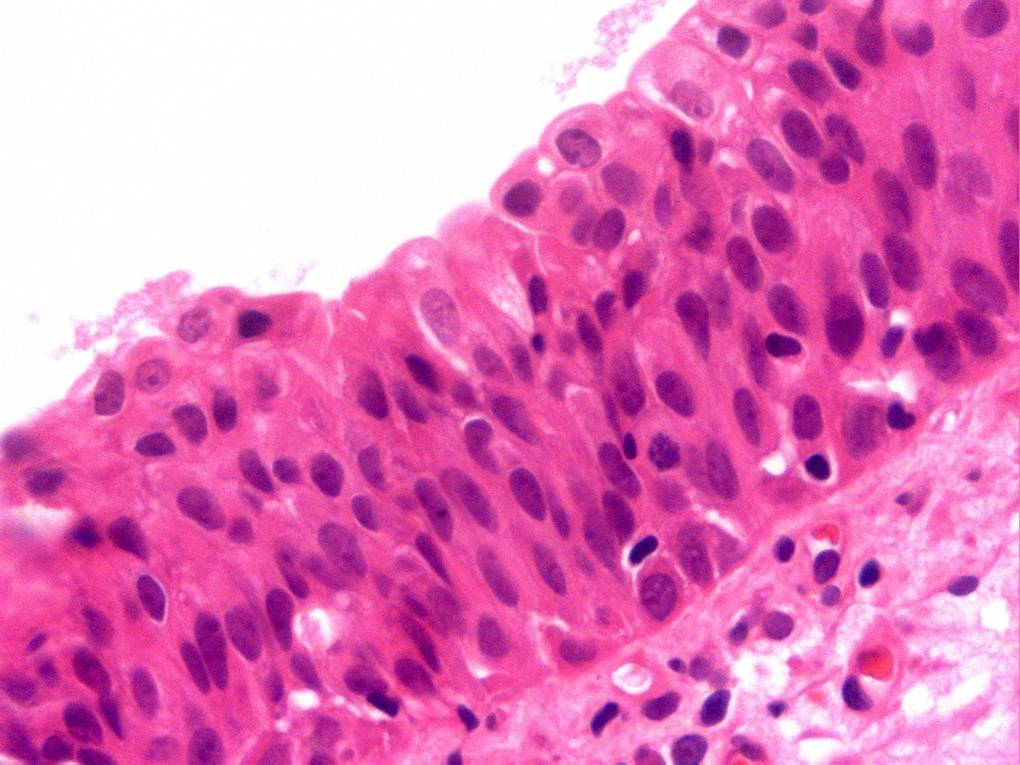

Bladder Flat Lesions

Case ID: 80